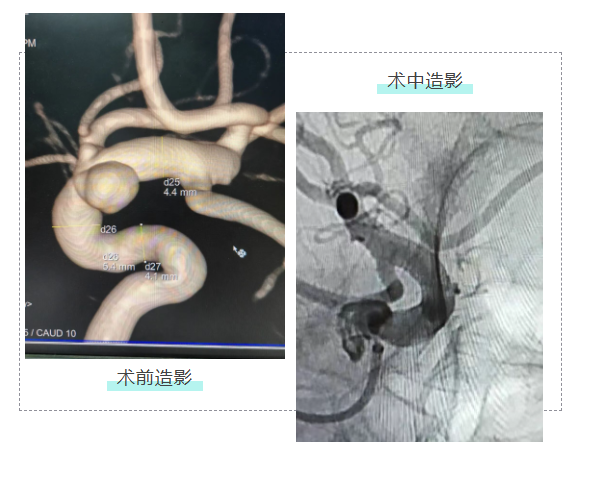

△术中造影显示,血流导向装置贴壁良好,动脉瘤内血流显著减慢,远端分支血管血流通畅。

手术当天,我院神经内科介入团队用时90分钟,将一根直径4.5mm的血流导向密网支架精准输送至患者动脉瘤所在的颈内动脉,缓慢释放后的支架如“隐形防护网”般贴合血管壁,完整覆盖瘤颈,患者术后即刻苏醒,无神经功能缺损,目前已康复出院。